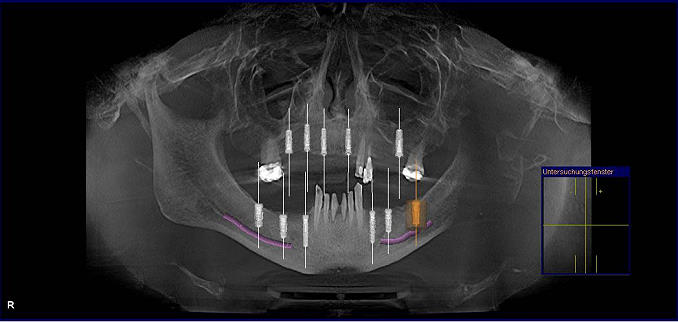

Die digitale Volumentomographie (DVT) ist die neueste technische Entwicklung bzw. eine Weiterentwicklung zur Computertomographie. Mit nur ¼ der Strahlenbelastung eines CT wird das Volumen des Ober- und Unterkiefers in nur 15 Sekunden aufgenommen. Die Daten stehen nach 8 Minuten zur Verfügung. In der Aufnahme sind sämtliche Grunddaten zur Planung einer Implantatversorgung enthalten. In dreidimensionaler Darstellung werden die Kiefer detailgetreu wiedergegeben und der Arzt kann in die einzelnen Strukturen hineinschauen und genaue Vermessungen vornehmen. Die genaue Position der Implantate in Länge und Durchmesser, sowie das Ausmaß an mangelnder Knochenhöhe und –breite kann bestimmt werden.